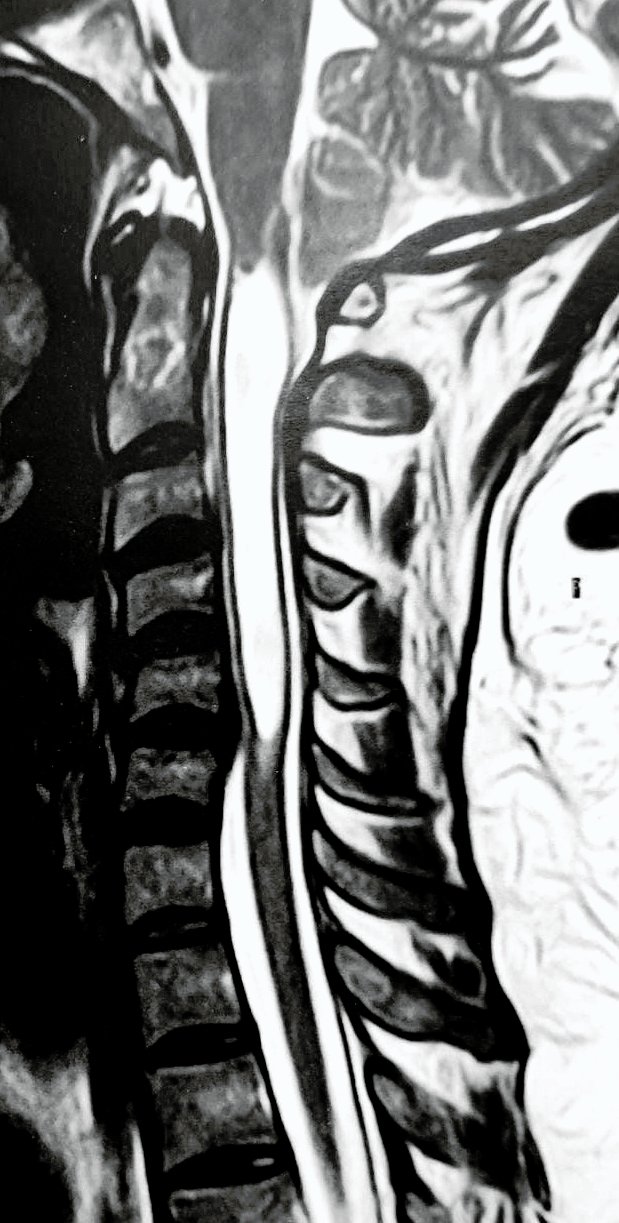

La siringomielia es una condición poco común que afecta la médula espinal. Se produce cuando aparece un quiste o cavidad dentro de ella, lo que puede causar presión o daño a los tejidos con el tiempo. Aunque puede sonar complejo, es importante saber que existen tratamientos y maneras de manejar la enfermedad para mejorar tu calidad de vida.

La siringomielia ocurre cuando el líquido cefalorraquídeo (LCR), que protege y nutre el cerebro y la médula espinal, no fluye como debería. Las causas de dicha obstrucción pueden ubicarse en la fosa craneana posterior (malformación de Chiari, quistes aracnoideos, etc.) o dentro de la columna vertebral (trauma, aracnoiditis, tumores, etc.).

El diagnóstico se realiza a través de una Resonancia Magnética (RM), un estudio indoloro y seguro que permite observar con detalle su médula espinal. Este examen es clave para confirmar la presencia y entender su impacto.